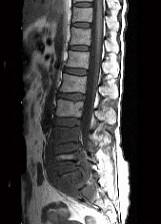

问题 男,35岁,曾有结核病史,现有午后发热,夜间盗汗等,腰部疼痛,活动时加重,休息后减轻,请结合所提供图像,选择最佳答案 ( )

选项 A、腰椎结核 B、多发性骨髓瘤 C、腰椎骨转移 D、腰椎退行性变 E、骨巨细胞瘤

答案 A